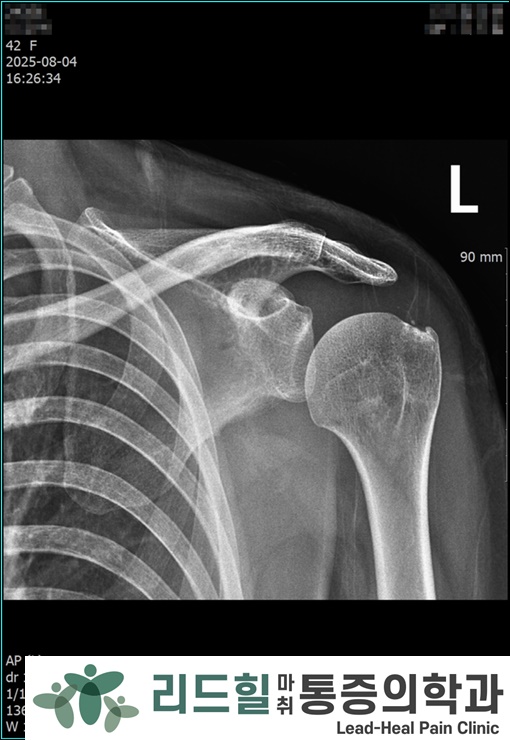

📸 6개월 후 X-ray

잔여 석회 거의 소실.

어깨 통증 완전 호전.

치료 종료.